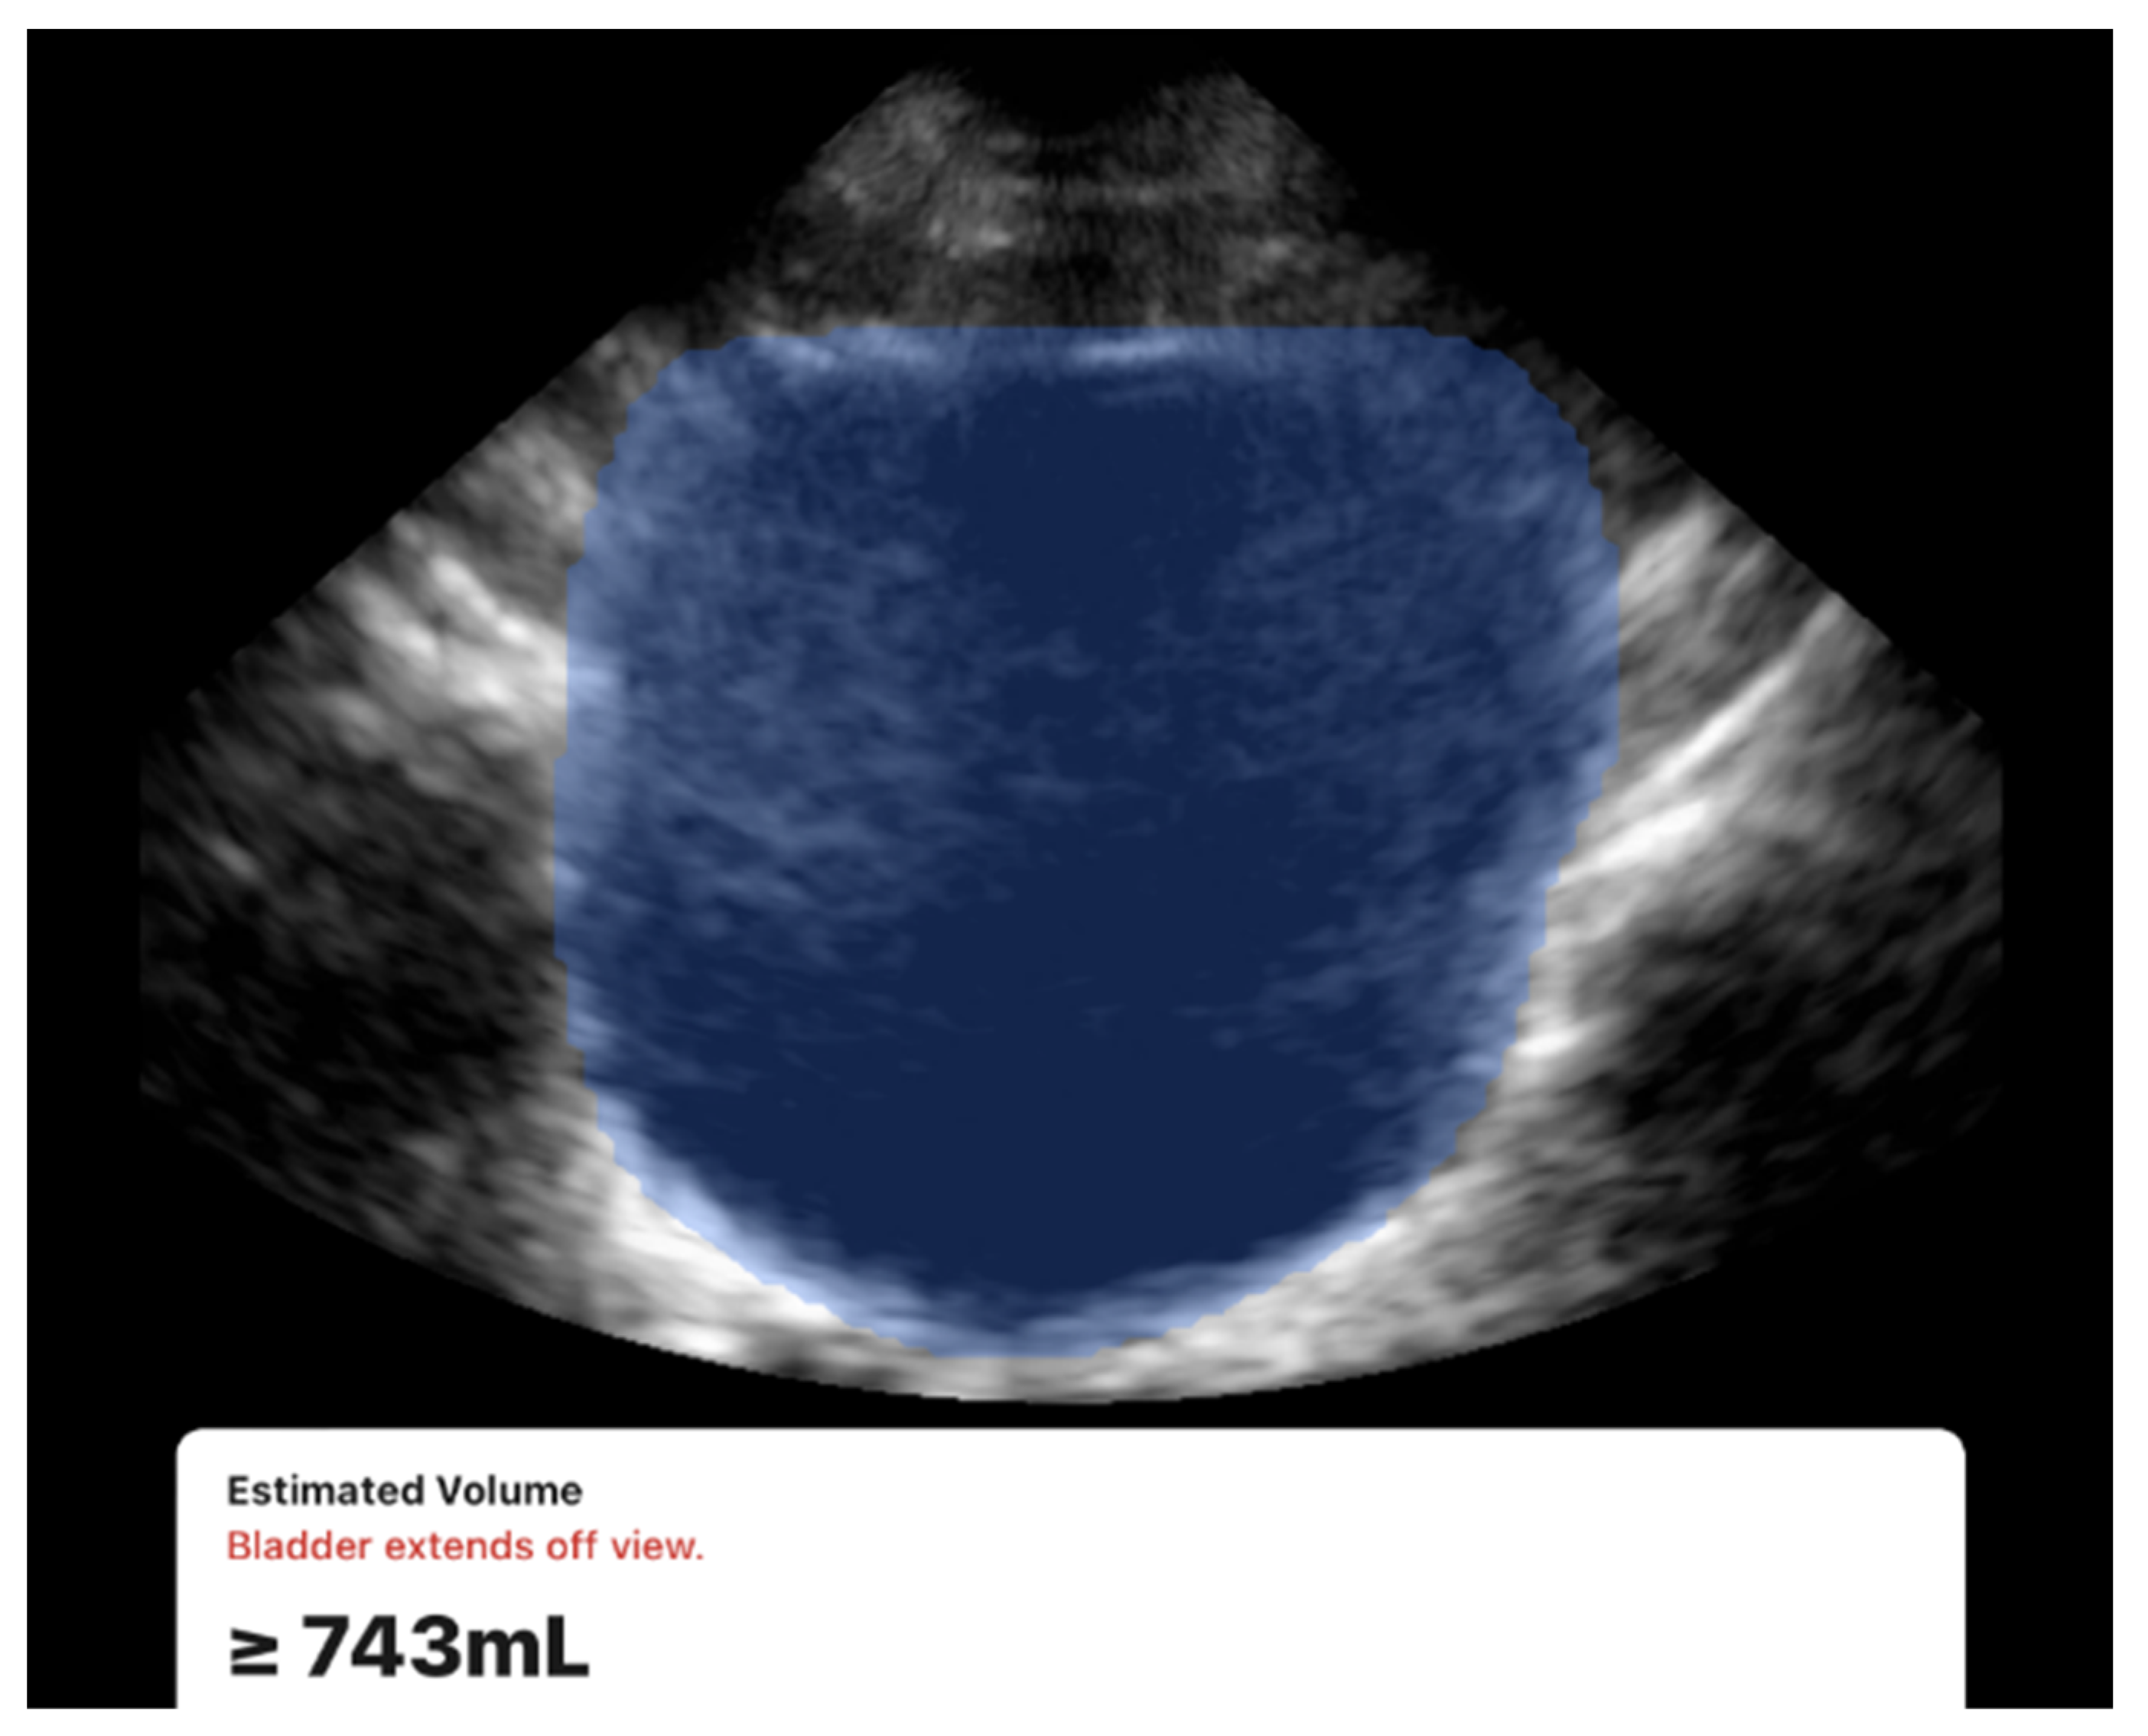

All scans were successfully completed with no missing data or technical difficulties during data acquisition. Examples of the acquired ultrasound images are presented in Figure 3 and Figure 4. While both devices were usable under all conditions, a limitation was observed with the 3D method. During acquisition, the Butterfly iQ device occasionally displayed a warning message stating “Bladder extends off view” (Figure 3). This occurred in 7 participants (13% of the cohort), all of whom had large bladder volumes (≥700 mL) or elongated bladder shapes. The issue is likely related to constraints in the probe’s electronic beam steering capabilities, which can limit capturing the full field of view. Despite this warning, the device continued to generate numerical volume estimates, and exclusion of these cases did not materially change the overall accuracy or reproducibility results.

One of the notable observations we found was the 3D method limitations with large bladder volumes (≥700 mL), where “bladder extends off view” warnings indicated field-of-view constraints. The literature supports our finding that bladder volume estimation is influenced by bladder size and shape, though most studies focus on accuracy rather than technical limitations. Vinod et al. demonstrated that both 3D ultrasound and BladderScan significantly underestimated bladder volumes, with 3D ultrasound showing a 30.1% error rate that improved to 20.7% after applying correction factors [13]. They also found that large, irregularly shaped bladders also produced greater underestimation errors. Bih et al. reported that bladder shape significantly affects volume estimation accuracy, with different correction coefficients needed for cuboidal (0.89), ellipsoid (0.81), and triangular prism-shaped (0.66) bladders [24]. The field-of-view constraint we observed likely represents a technical limitation of the Butterfly iQ handheld ultrasound device when encountering extremely distended bladders, which may have more irregular shapes that exceed the electronic beam steering capabilities. This suggests that while 3D automated methods offer superior accuracy for most clinical scenarios, alternative techniques may be necessary for patients with very large bladder capacities, particularly those with neurogenic bladder dysfunction who are more likely to develop both large volumes and irregular shapes.

Figure 3. Example of the 3D method scan using the Butterfly iQ device showing the automated bladder volume estimation. Note the “Bladder extends off view” warning which was often observed in cases with large bladder volumes.